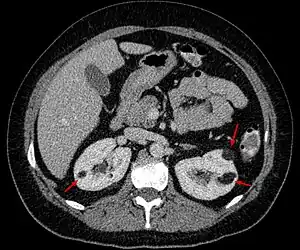

| Angiomyolipoma in both kidneys (arrows) in computer tomography. The tumours are hypodense (dark) due to fat content. | |

Angiomyolipomas are strongly associated with the genetic disease tuberous sclerosis, in which most individuals have several angiomyolipomas affecting both kidneys. They are also commonly found in women with the rare lung disease lymphangioleiomyomatosis. Angiomyolipomas are less commonly found in the liver and rarely in other organs. Whether associated with these diseases or sporadic, angiomyolipomas are caused by mutations in either the TSC1 or TSC2 genes, which govern cell growth and proliferation. They are composed of blood vessels, smooth muscle cells, and fat cells.